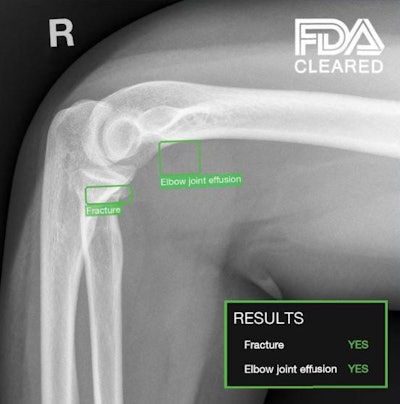

TechCare Trauma. Image courtesy of Milvue.

The software enables real-time detection and localization of fractures and elbow joint effusions on x-rays. TechCare Trauma is designed for use in both adults and children and was validated in a study that included more than 7,000 U.S. patients, the company said. It has demonstrated high accuracy and consistent performance across different anatomical regions, imaging views, patient demographics (age and sex), imaging hardware manufacturers, and in both displaced and nondisplaced fractures, according to the vendor.